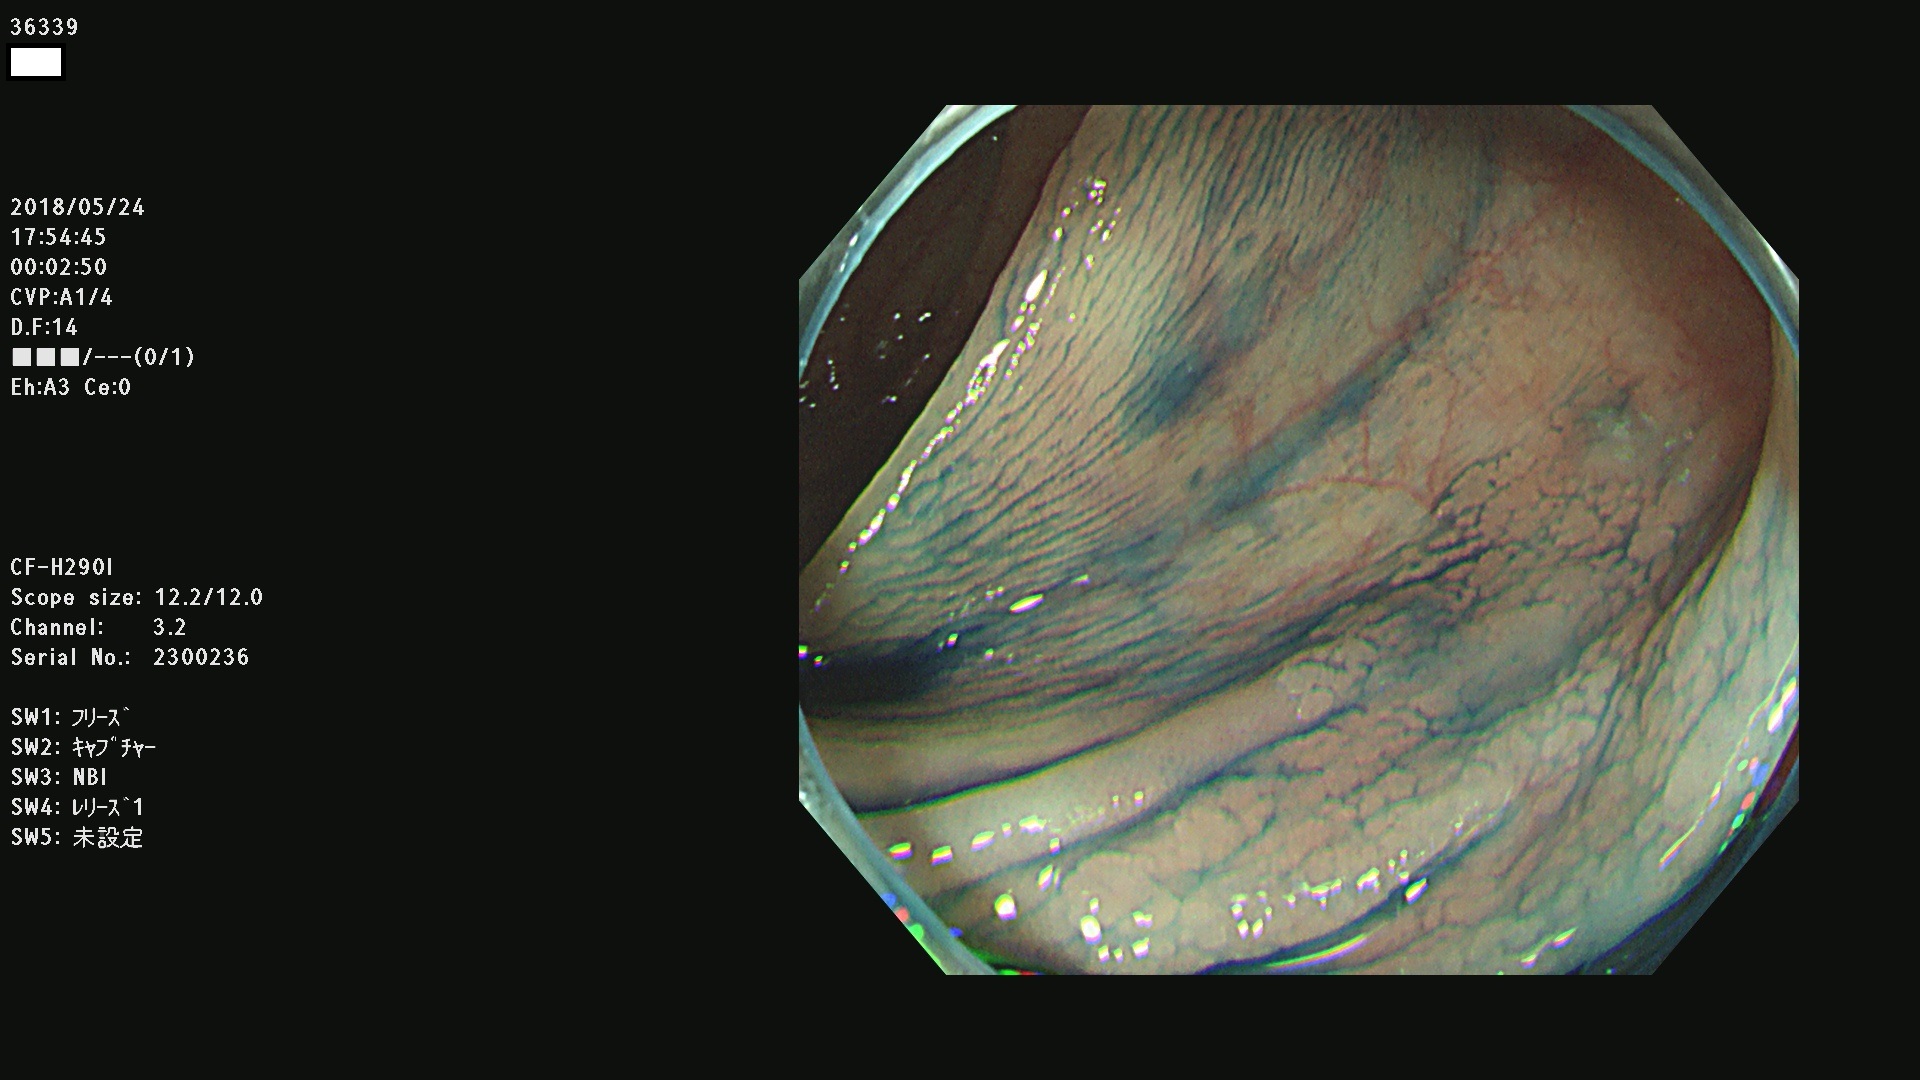

腺腫発見率 68 % (カルテ番号 36300〜36399の100名の方の検査結果で集計)大腸癌検診最新情報

以下のカルテ番号の方に腺腫(Adenoma,Group3〜5)が見つかりました(集計法)

36300 36302 36305 36306 36307 36308 36310 36311 36312 36313 36314 36315 36316 36318 36321 36322 36324 36325 36326 36327 36330 36332 36333 36334 36335(SSAPのみ) 36337 36338 36339(SSAPのみ) 36340 36341 36342(SSAPのみ) 36343 36344 36346 36348 36349 36351 36353 36354 36355(SSAPのみ) 36356 36357 36358 36359 36364 36365 36366 36367 36370 36374 36376 36379 36381 36382 36383 36384 36385 36387 36388 36389 36390 36392 36393 36395 36396 36398 36399

発見困難で危険性の高い平坦型病変(上記100名より抽出) ![]()